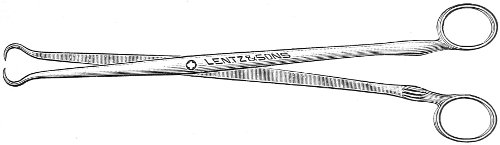

Fig. 4.—Double tenaculum.

The examination of the uterus and other pelvic structures is often facilitated by dragging the uterus downward with a tenaculum while the vaginal or the bimanual examination is being made. Sensation in the cervix is so slight that little or no pain is experienced in this procedure. The anterior or posterior lip of the cervix is caught with the single or the double tenaculum (Fig. 4), guided along the vaginal finger or introduced through the speculum, and the uterus is drawn down by an assistant in case the bimanual examination is being made, or by the external hand of the examiner in case a simple vaginal examination is made. When this is done the utero-sacral ligaments are made tense, and can be felt like two cords extending from the sides of the cervix outward and backward to the pelvic wall. The posterior surface of the uterus can be palpated often as high up as the fundus. The method is especially useful when the examination is made by the rectum, and in this way the whole posterior surface and the fundus of the uterus may be palpated (Fig. 5).